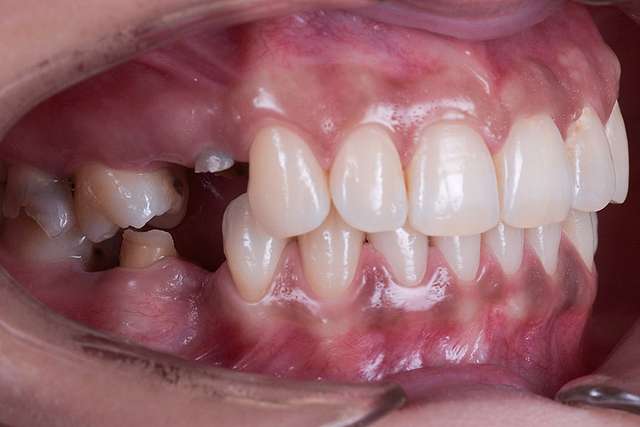

Chirurgia ghidata, ne faciliteaza o pozitie ideal pre-planificata, care nu tine cont doar de os, ci si de o pozitie optima in relatie cu viitorul dinte.Chirurgia ghidata înseamnă o precizie crescuta, care inseamna siguranta mai mare, timp operator mai scazut, si trauma mai mica. De asemenea focusul in acest tip de interventii a migrat spre reconstructia tesuturilor, care e pe termen lung are un impact mult mai mare atat estetic cat si biologic, inserarea implantului in sine fiind trivializata de folosirea ghidului chirurgical. Cazul de fata este un exemplu al acestui tip de abordare.